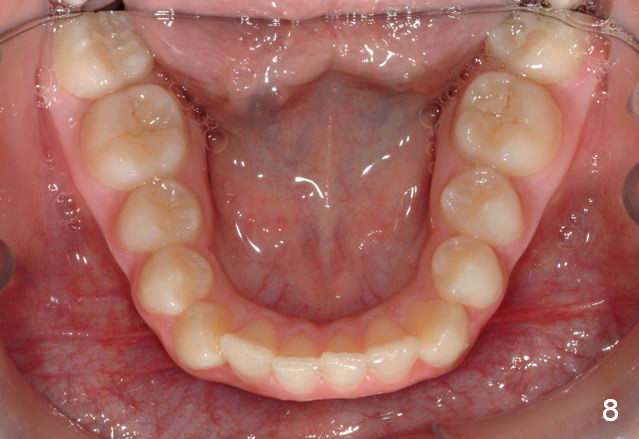

Unilateral Class II Malocclusion

The upper dental midline deviates to the left (Fig.2,4). Facial profile is normal (Fig.3). The right molar relationship is Class II (Fig.5), while the left one is normal or slightly Class III (Fig.6). How to treat?